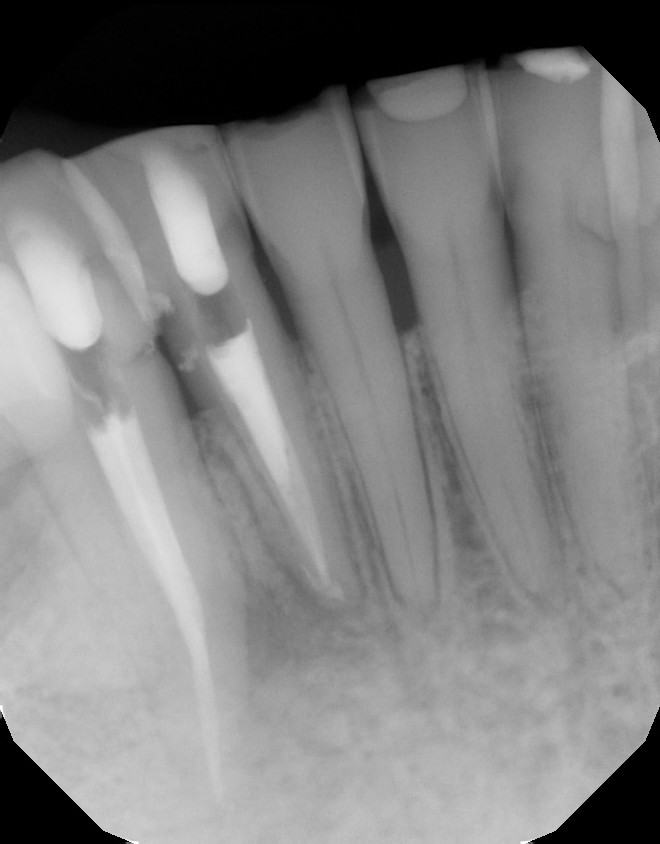

| Necrotic pulp with sinus tract on the buccal of #26. |

| CBCT shows the apical and lateral bone loss on #26 and #27. The lateral bone loss on #27 is also suggestive of a possible root fracture, but since the tooth is necrotic, radiographic appearance alone is not enough evidence to diagnose this with a root fracture. CBCT also shows a 2 canaled root form on #26. |

| There was concern of a possible root fracture, but none could be see internally with microscope. CaOH medicated dressing was placed after initial debridement and NaOCl irrigation. |